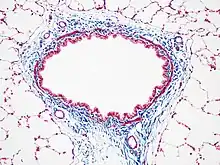

Masson's trichrome stain of rat airway. Connective tissue is stained blue, nuclei are stained dark red/purple, and cytoplasm is stained red/pink.

Most recipes produce red keratin and muscle fibers, blue or green collagen and bone, light red or pink cytoplasm, and dark brown to black cell nuclei.

Another common variant is the Masson trichrome & Verhoeff stain, which combines the Masson trichrome stain and Verhoeff's stain.[2] This combination is useful for the examination of blood vessels; the Verhoeff stain highlights elastin (black) and allows one to easily differentiate small arteries (which typically have at least two elastic laminae) and veins (which have one elastic lamina).